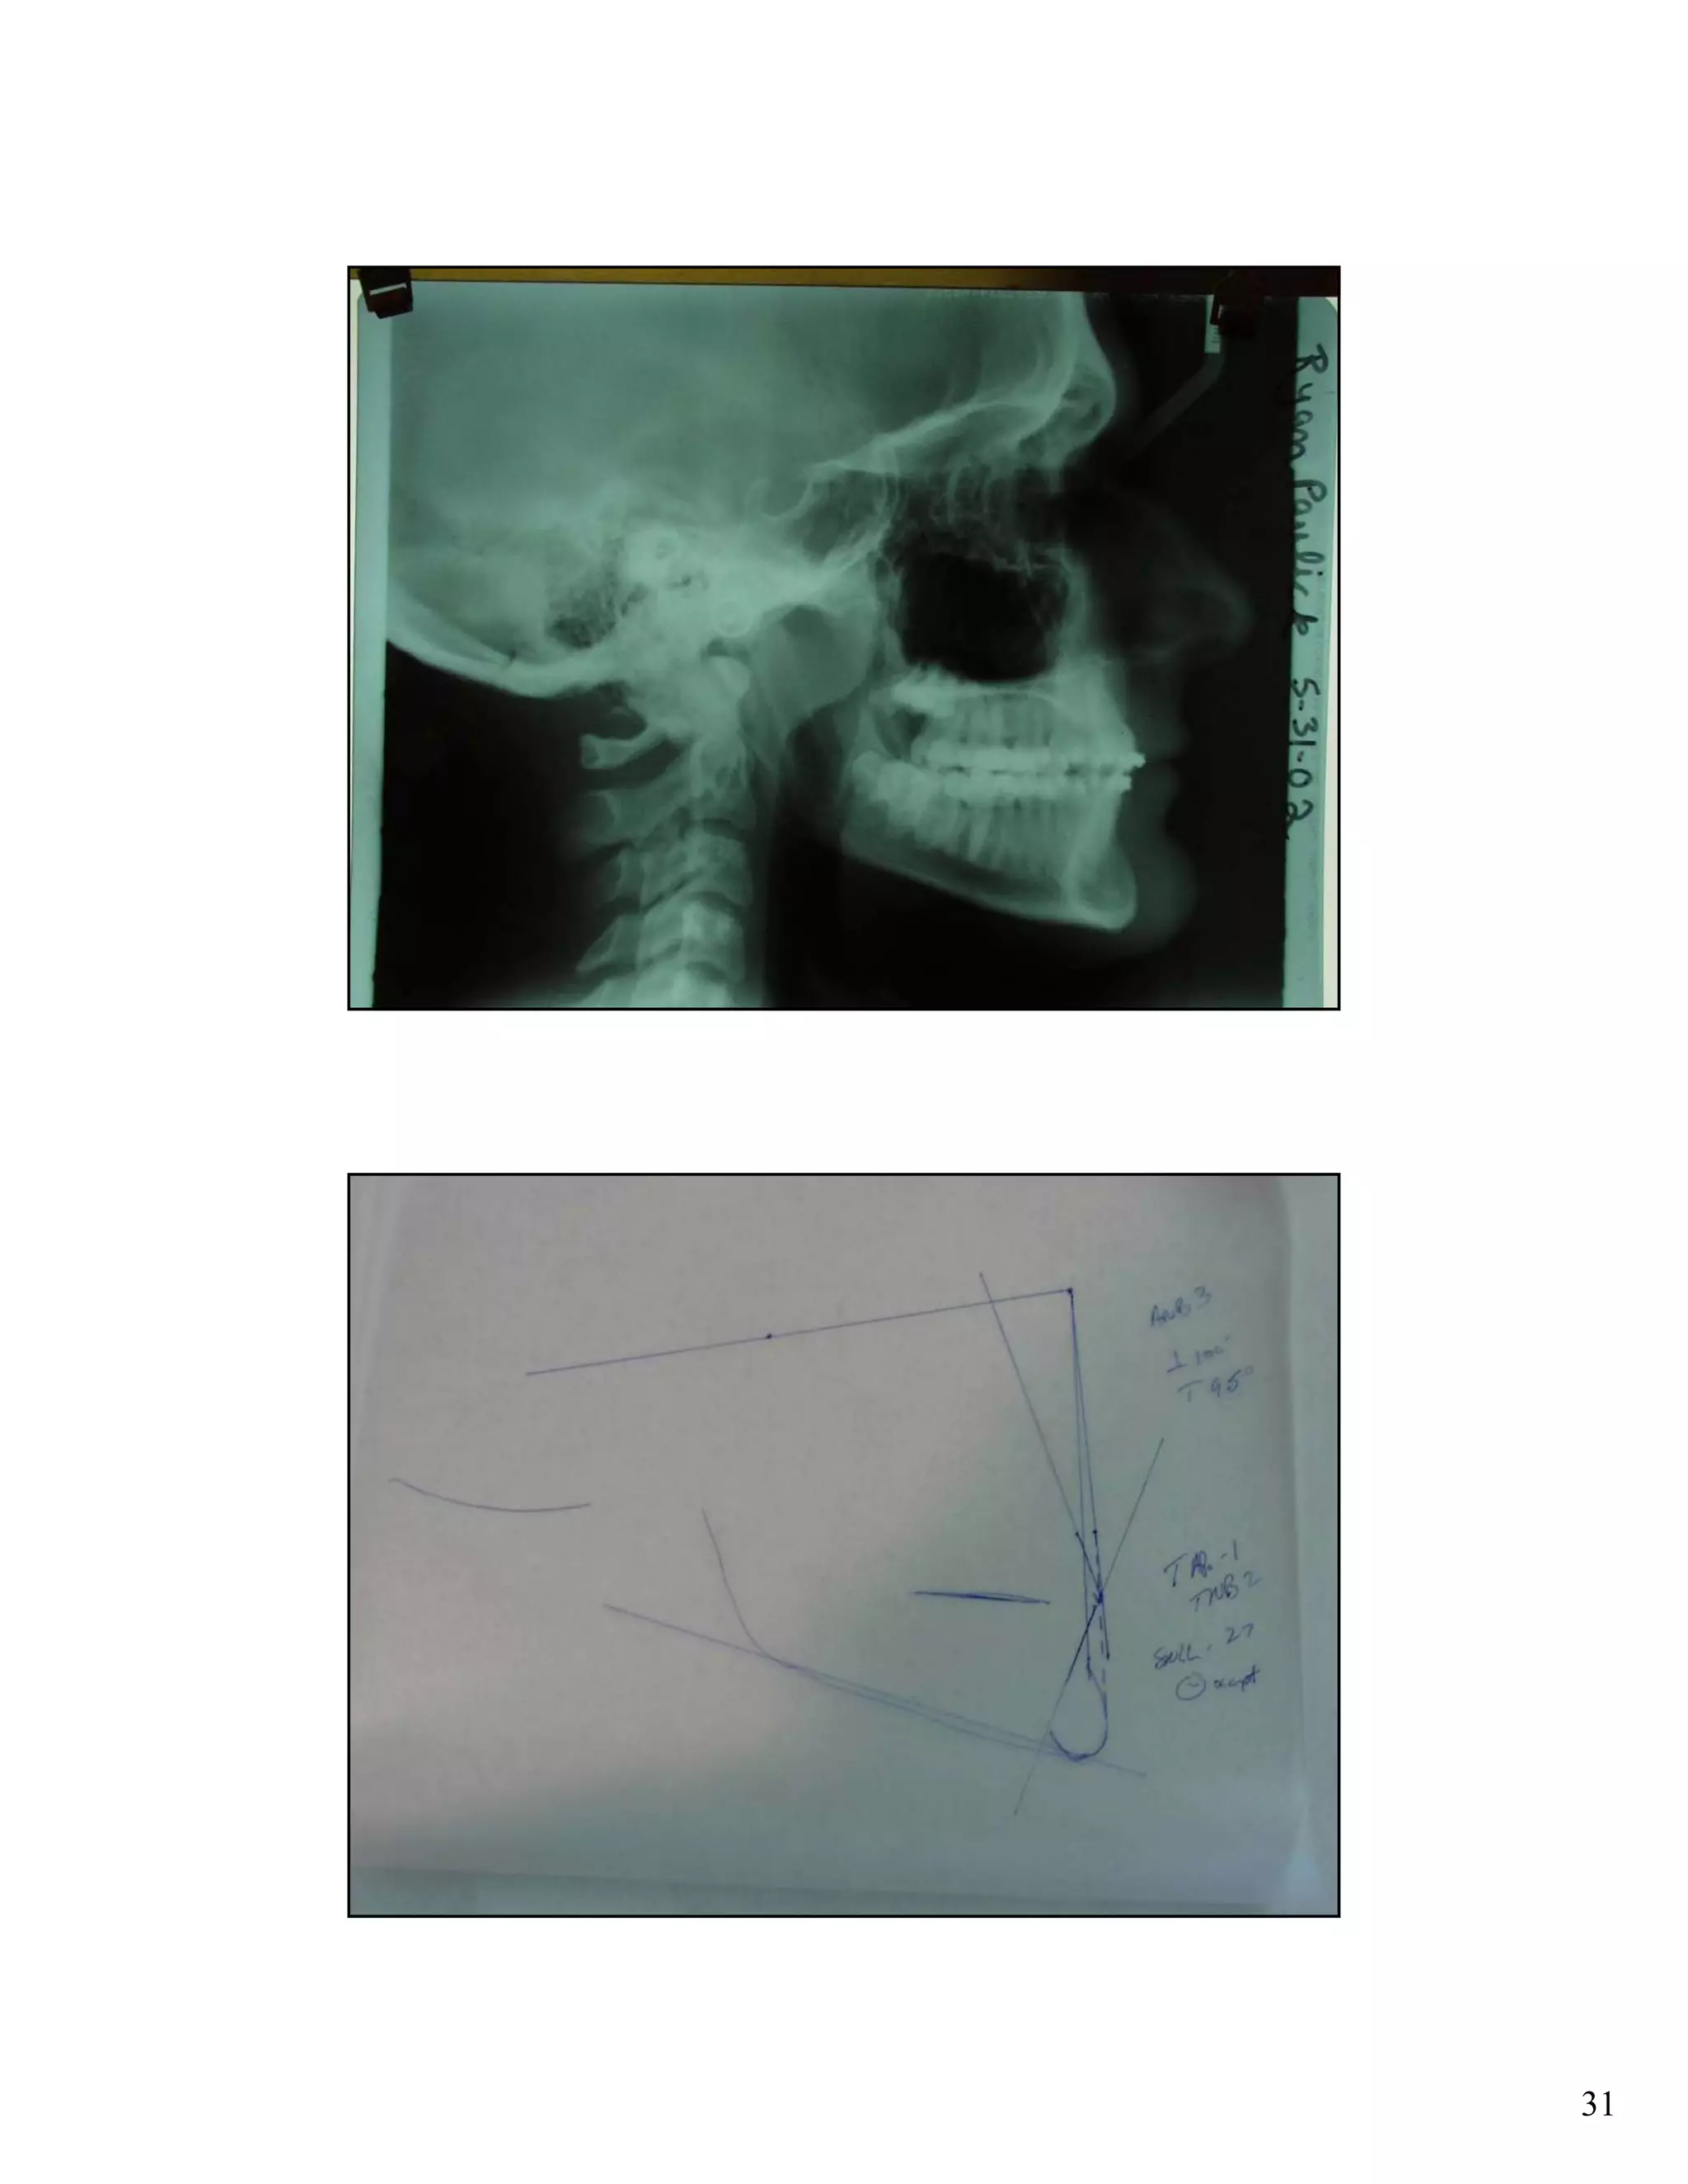

Cephalometric analysis uses x-rays of the skull to measure the growth and development of facial structures. Key indicators include the SN:GoGn angle measuring lower facial growth direction, the S-Go/N-Me ratio comparing posterior and anterior facial heights, and extension of the GoGn line to the occiput. These measurements help assess growth trends and plan orthodontic treatments.